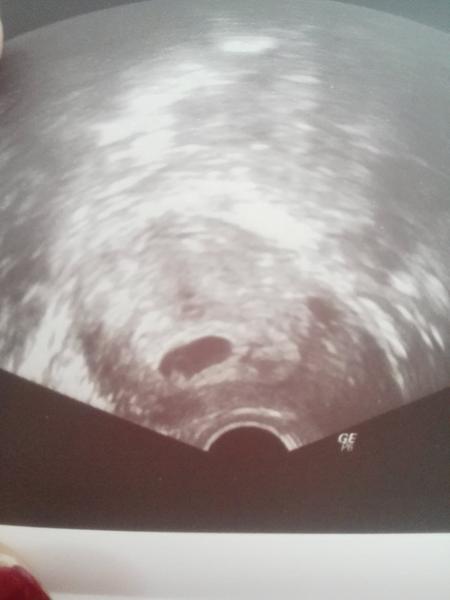

Ahoj holky, poprosila bych vás o radu či názor... Mám 4 dny zpoždění, což u mě nebývá vůbec běžné a na testech se mi včera a dnes ukázal "duch" (2 testy každý den a na všech byl).. Fotka trochu zkresluje a Dušík byl trochu víc vidět, ale přesto nic extra výrazného... Myslíte, že je to nadějné?